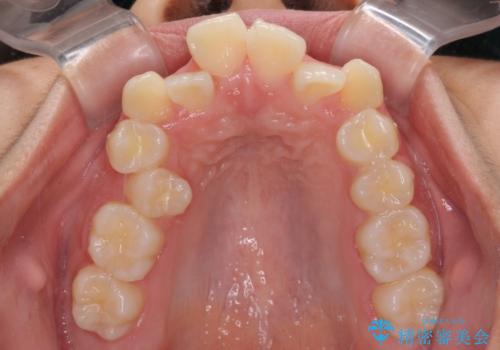

- 歯列全体の叢生を気にして来院された患者様です。

検査を行った結果、上顎骨の横幅が相対的に狭いことが分かり、叢生が強いことから、急速拡大装置にて上顎骨を側方に拡大することで、叢生の解消と奥歯の咬み合わせ改善を図ることとしました。

一般的には上下左右の第一小臼歯4本を抜歯する必要がありますが、拡大量によっては非抜歯矯正の適用となる可能性があるため、まずは非抜歯矯正で治療を開始し、抜歯が必要と判断された時点で速やかに4本抜歯を行うこととしました。

急速拡大後、歯列はきれいに並んだのですが、口元が出っ歯になってしまったため、速やかに抜歯を行い、治療期間がいたずらに遅延することのないようにしました。